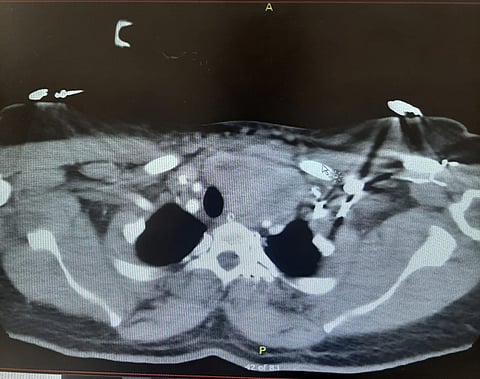

الفحوصات الطبية والأشعة كشفت عن تضخُّم كبير بالغدة الدرقية مع امتداد إلى الجزء العلوي من التجويف الصدري، واعوجاج في القصبة الهوائية.